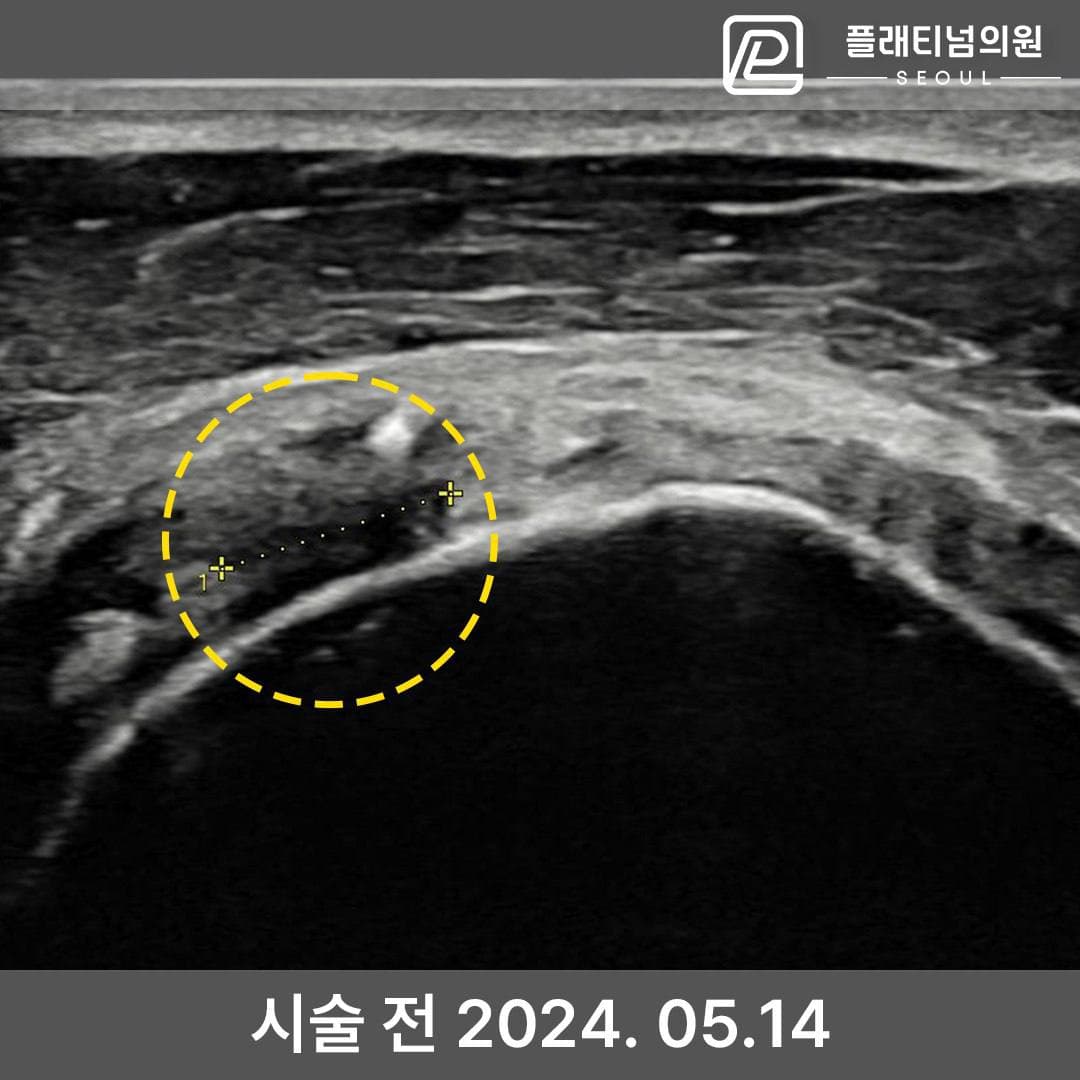

인대재생주사 시술 전후 초음파

실제 환자의 시술 전후 초음파 비교입니다. 파열되어 결손이 있던 인대 조직이 시술 후 회복된 것을 확인할 수 있습니다.

4세대 인대재생주사 시술 후 초음파 확인 결과

인대 조직 재생 확인 — 시술 전후 비교

* 개인차가 있을 수 있으며, 모든 환자에서 동일한 결과를 보장하지 않습니다.